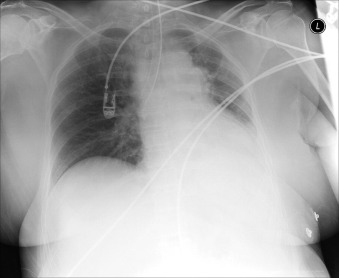

Complications of intubation ( Figs. 25-1 to 25-10 ) and ventilation that are apparent on a chest radiograph are often potentially life-threatening and should be excluded on every radiograph, both immediately following intubation and with each subsequent radiograph. These possibilities are listed in the following sections.

Barotrauma

Pneumothorax

Pneumomediastinum

Pneumopericardium

Subcutaneous emphysema